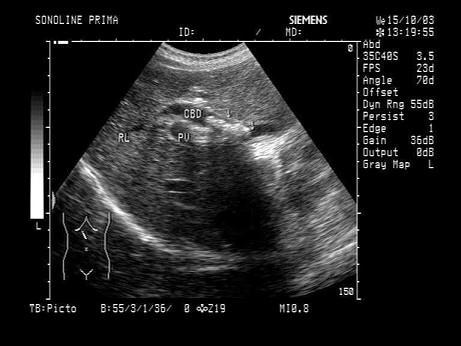

问题 女,48岁,上腹部剧烈疼痛2天。皮肤巩膜轻度黄染。声像图如图所示,诊断为?(?)

选项 A.胆总管蛔虫 B.胆总管胆汁淤积 C.胆总管结石 D.胆总管癌 E.胆总管腺瘤

答案 C